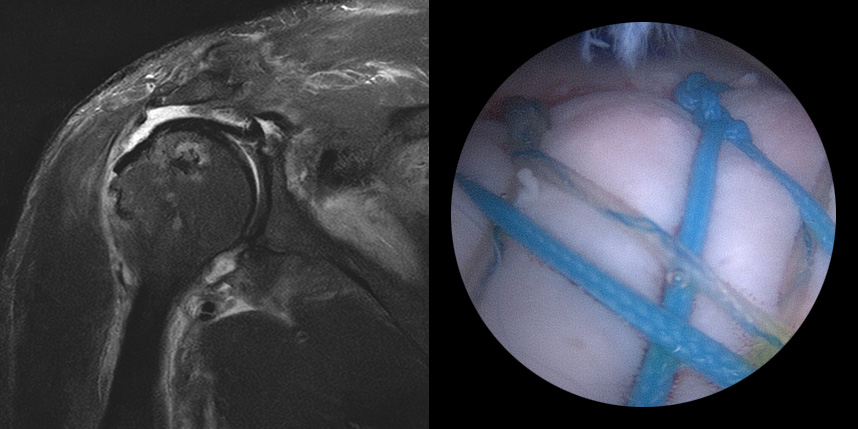

5mm 내외의 최소 절개 후 내시경을

삽입하여 치료 부위를 확인합니다.

의사가 치료 부위를 직접 확인하면서

손상된 조직을 봉합 혹은 제거 합니다.